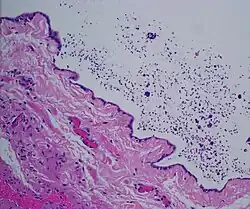

The primary care physician may diagnose and manage benign causes of scrotal masses such as hydrocele, varicocele and spermatocele. However, if a "must not miss" diagnosis related to testicular masses such as testicular torsion, epididymitis, acute orchitis, strangulated hernia and testicular cancer is suspected, the family physician must refer to a urologist.[19] Finding a painless, cystic mass at the head of the epididymis that is clearly separate from the testicle can indicate a spermatocele. Shining a light through the mass, a process known as transillumination, can also help differentiate between a fluid-filled cyst and a tumor, which would not allow as much light to pass.[20] If uncertainty exists, ultrasonography of the scrotum can confirm the presence of a spermatocele.[7] The location and history of any scrotal masses are crucial in determining whether or not the mass is benign or malignant.[21] Lab tests such as a complete blood count (CBC test) or urine test can also be conducted to check for any possible infection or signs of inflammation.[22]

Spermatoceles come in varying sizes and shapes. Some spermatoceles are very small and can only be detected through an ultrasound. More commonly seen are spermatoceles that are a pea-sized lump. They tend to form above or behind a testicle and have a shape and size that looks like a pea. Larger growths have been reported to look similar to a third testicle and can be very discomforting.[22] For those who are affected with large spermatoceles, some have reported feeling pain, heaviness, and fullness in the affected testicle.[20]